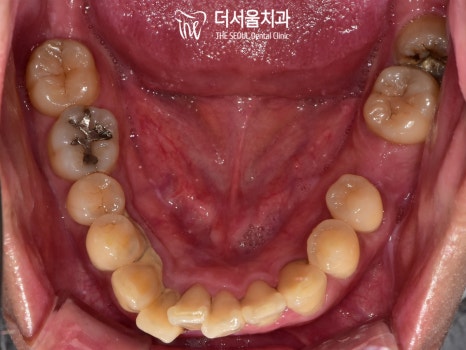

음 그런데 문제는 하나가 아니네요.

이미 빠져있는 치아도 존재했으며

심하게 썩은 곳도 볼 수 있었습니다.

상악에서는 검게 남아있는 잔존 치근과

군데군데 썩은 곳들이 눈에 띄는데요.

하악도 마찬가지였습니다.

이미 상실되어 빈자리로 남아있는 어금니와

심하게 썩어있는 사랑니,

이외에도 크고 작은 우식을 발견할 수 있었죠.

전체적으로 상황이 좋은 편은 아니었습니다.

전과는 달리 검게 썩어 있던 곳들이

모두 개선되어 있는 것을 확인할 수 있습니다.

크고 작은 충치들도

근관치료, 인레이, 레진을 사용하여

개선해드렷습니다.